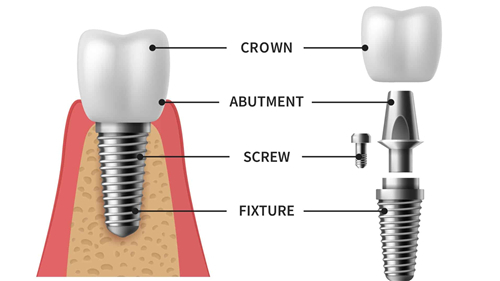

国产种植牙:6000元起

韩国进口种植牙:6500元起

美国进口种植牙:9000元起

德国进口种植牙:9500元起

瑞士进口种植牙:13000元起

瑞典进口种植牙:16000元起